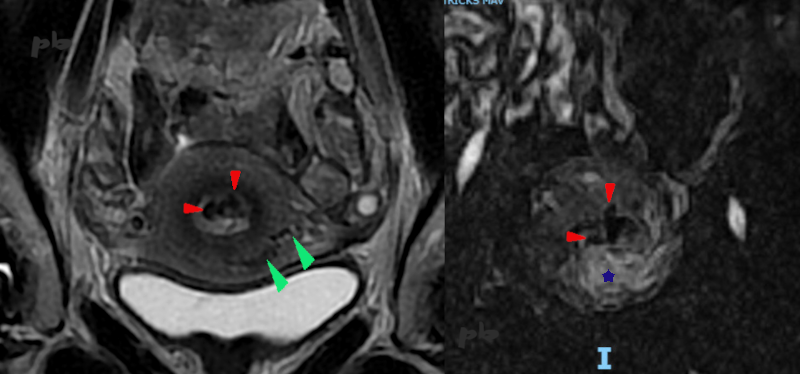

IRM coupes frontales, T2 à gauche et séquence vasculaire injectée (Tricks) à droite.

Fausse couche il y a 2 mois. Traitement médical. Une 1ère échographie avait mis en évidence des résidus avec faible résistance vasculaire et une afférence de l’artère utérine.

Sur les 2 coupes, images de vide de signal (noires ►) dans l’endomètre : vaisseaux à flux rapides.

Présence d’images identiques dans le myomètre (►). A ce niveau, le myomètre s’opacifie plus vite (★) que dans le reste de l’utérus.